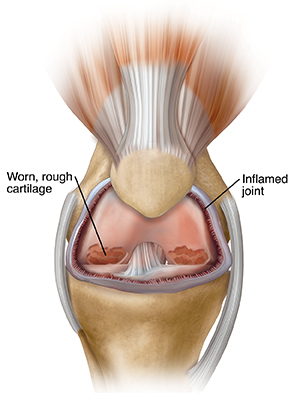

A problem knee

A problem knee is often stiff and painful. Cartilage cracks or wears away due to usage, inflammation, or injury. Worn, roughened cartilage no longer lets the joint glide freely. So it feels stiff and painful. As more cartilage wears away, exposed bones rub together when the knee bends, causing pain. With time, bone surfaces also become rough, making pain worse.